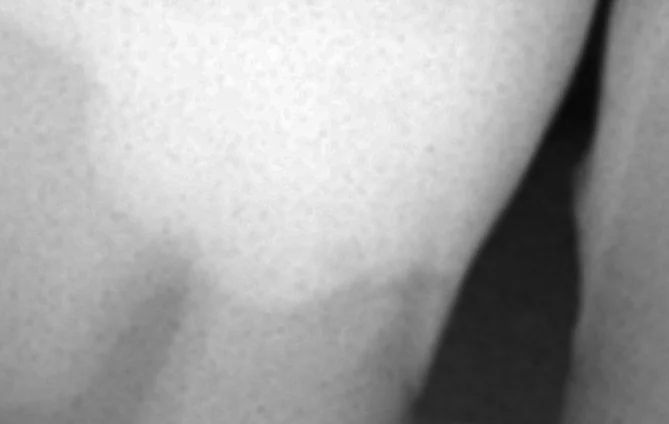

そして詰め終わった同じ部分のレントゲンがこちらです。

歯から詰めた部分に段差が一切ないのが分かりますかね?

黒い部分(虫歯)も完全になくなっているので、綺麗に治っているのが分かるかと思います。

適合はしっかりと合わせているので、生活習慣次第では非常に長く持たせることが可能だと思います。